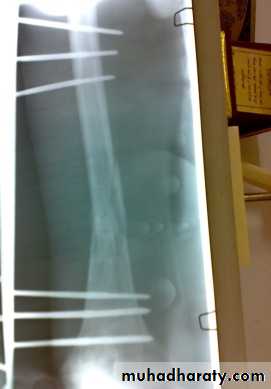

Open fractures treated by debridement and external fixation.

Definitive treatment

closed fractures: by Open reduction and internal fixation, this will decrease the systemic complications.

Fixation of femoral shaft fracture